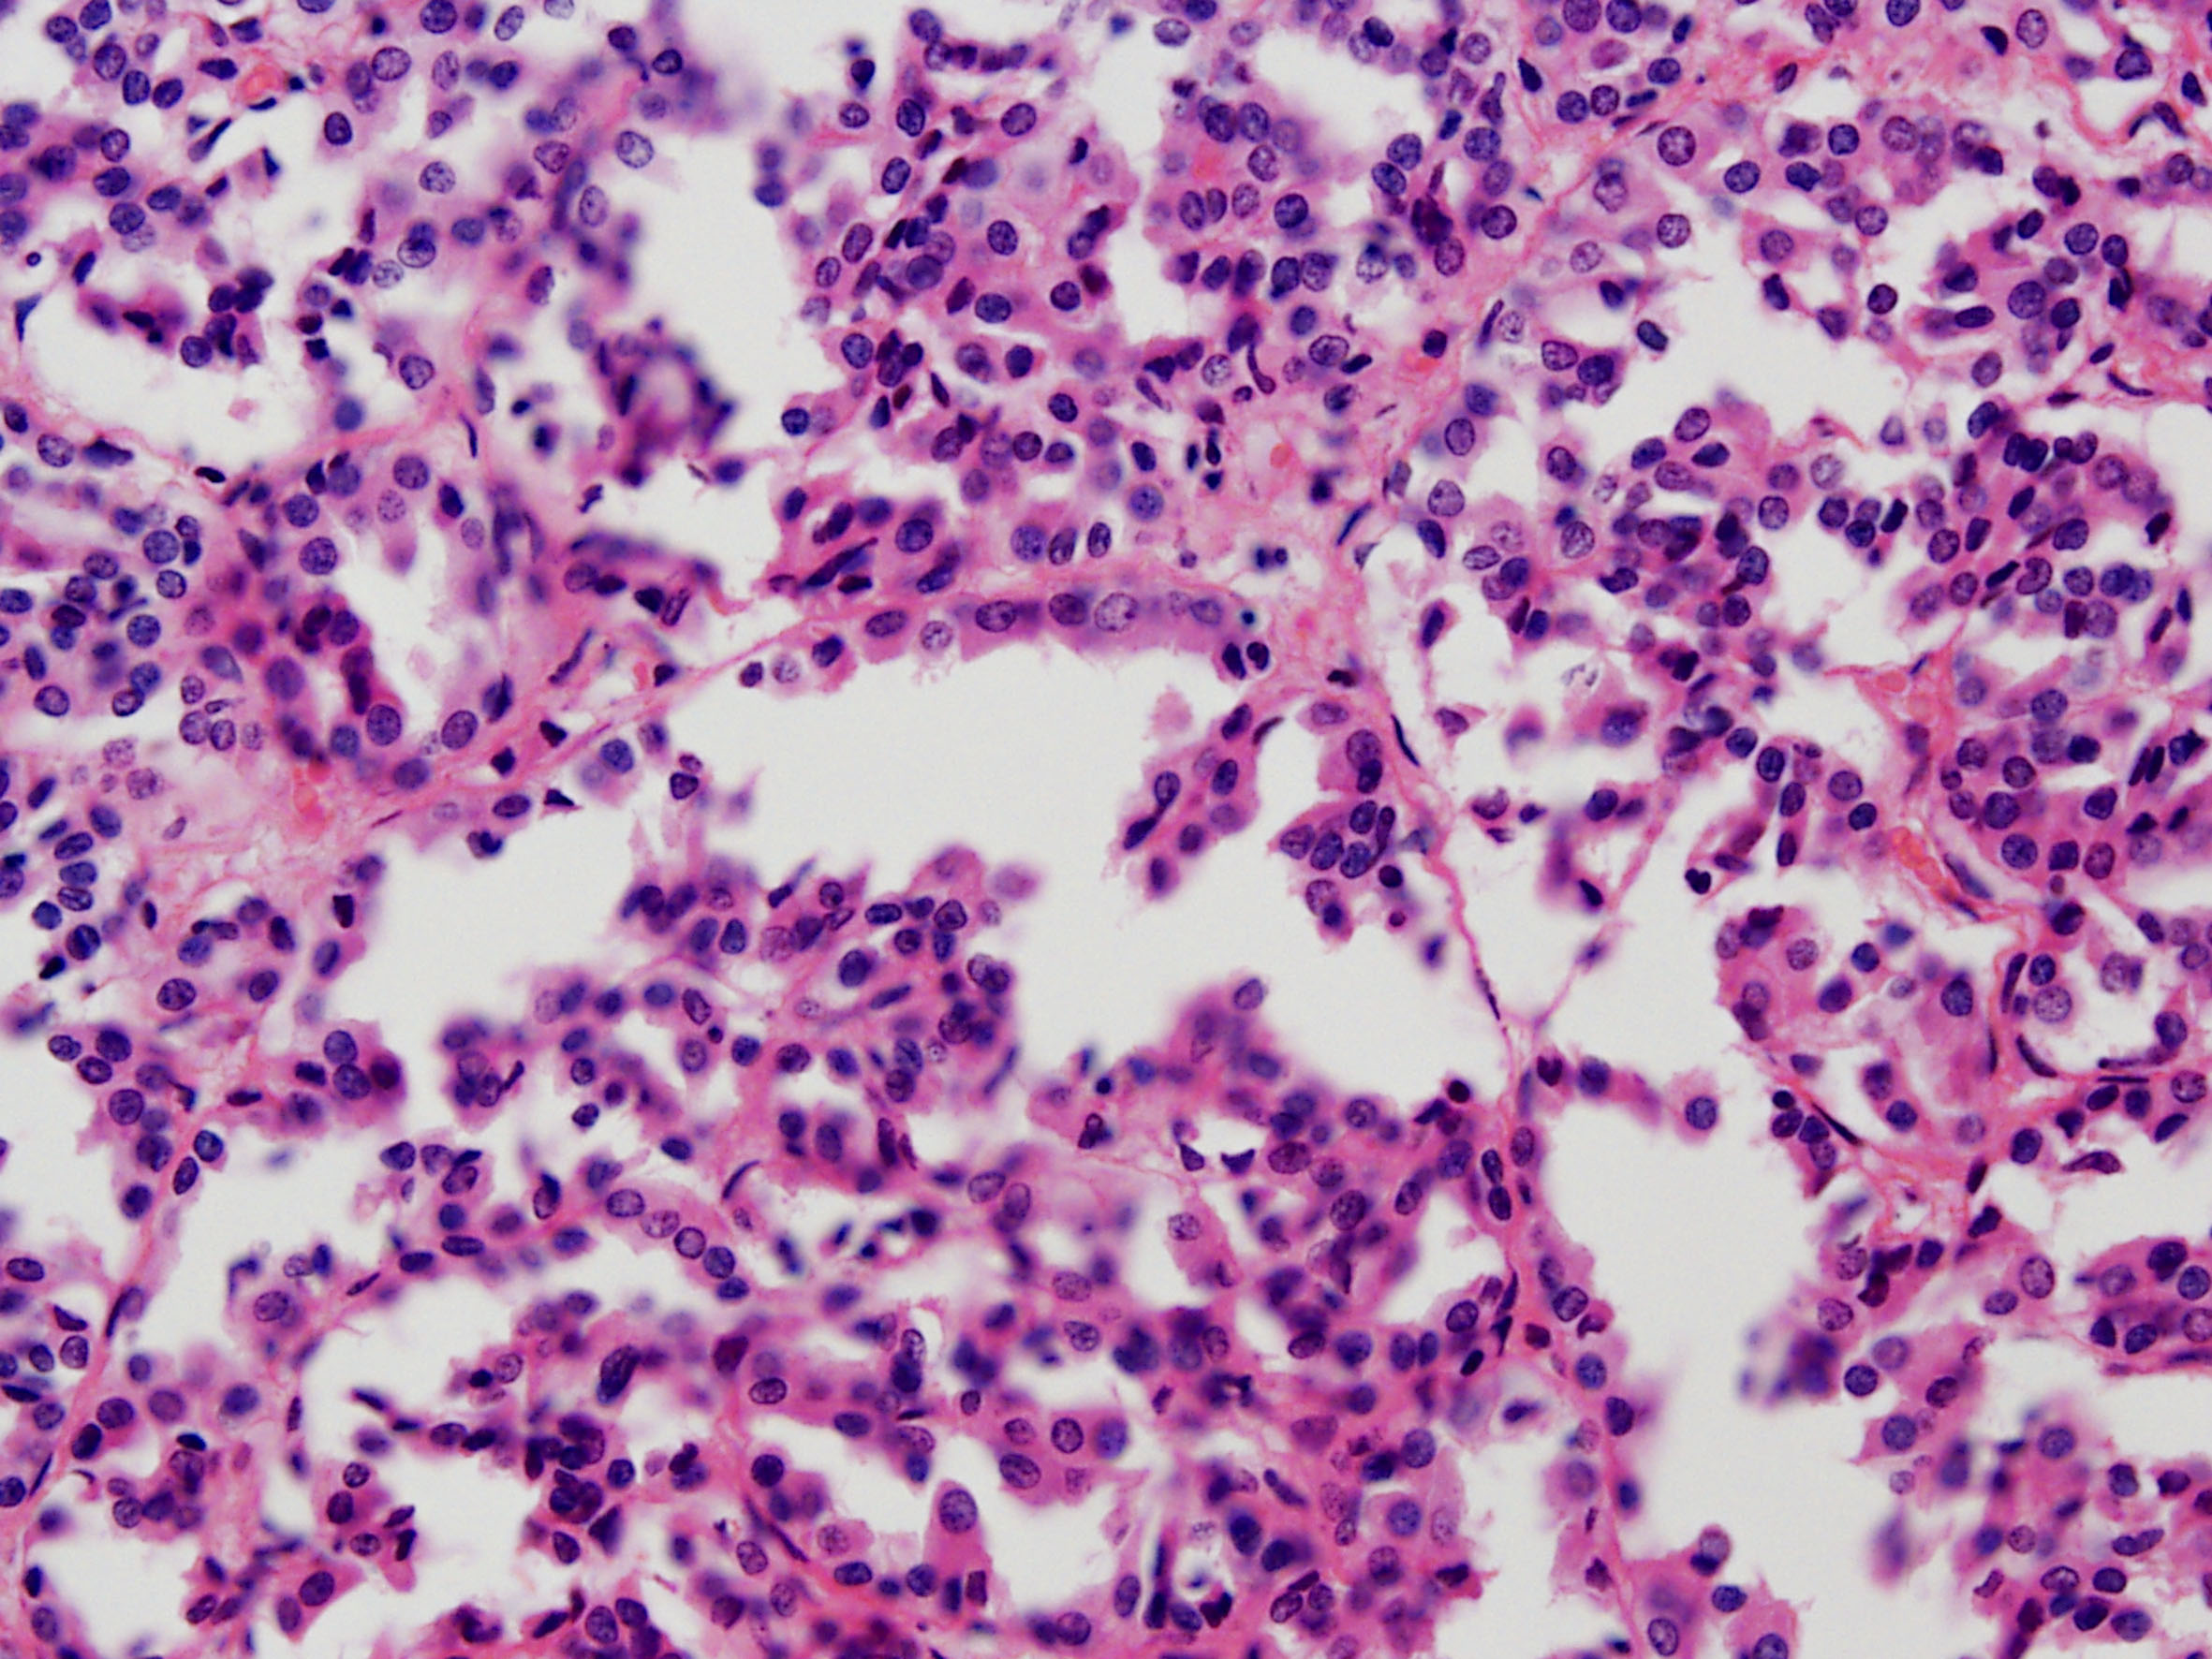

Case description (by case creator):

Papillary adenoma